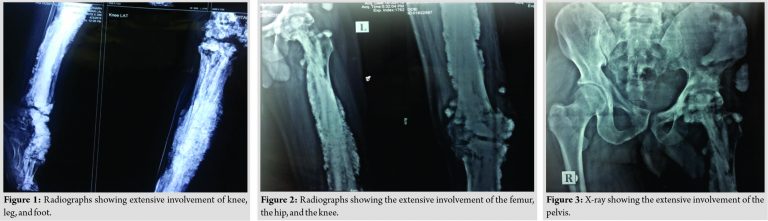

Case Report: We describe a highly unusual and extensive involvement of the lower limb in a Melorheostotic patient of 35 years of age with a deformity and limb length discrepancy. X-rays are like that of myositis ossificans and mixed type of pattern with extensive involvement from the pelvis to the toe. There is also intra-articular extension of melorheostosis mimicking synovial chondromatosis. The patient is in our close follow-up and physiotherapy guidance. Such an extensive involvement, along with para-articular and intra-articular involvement, is very rare.

There was a flexion deformity of 30° of the knee and equino cavo varus deformity of the foot and the ankle. There was a limb length discrepancy of 7 cm. The patient was ambulatory without any walking aid. There was no sensory loss. Laboratory tests, including complete blood count, erythrocyte sedimentation rate, C-reactive protein, serum calcium, phosphorus, and alkaline phosphatase, were within normal limits. Other tests, including renal function tests, liver function tests, T3, T4, thyroid-stimulating hormone, and parathyroid hormone, were normal. X-rays characteristically showed dense sclerotic nodular, hyperostotic lesions involving the pelvis, femur, tibia, fibulae, and the 1st and 2nd toes. Knees and ankle also showed intra-articular/para-articular involvement. Such an extensive involvement right from the pelvis to toes, including the knee and ankle, has not been reported before. The X-rays did not precisely fit into any of the patterns described in the literature; rather they were of the mixed type.

Whole-body bone scan was performed, which showed increased uptake in the left femur, pelvis, tibia, fibula, and foot. The biopsy was taken from the distal femur which showed the abundance of osteoid formation with hypercellular compact lamellar bone pattern. No endochondral ossification, synovial tissue, fibroblasts, or calcification were present, and there was no zonal pattern, hence ruling out both synovial chondromatosis and myositis ossificans. No cartilaginous material was identified. Understanding the complexity of the treatment of deformities and anticipation of multiple surgeries, the patient refused for surgery of any kind but is in close follow-up, bisphosphonate therapy, analgesics, and physical therapy guidance (Fig. 1, 2, 3, 4, 5, 6, ).